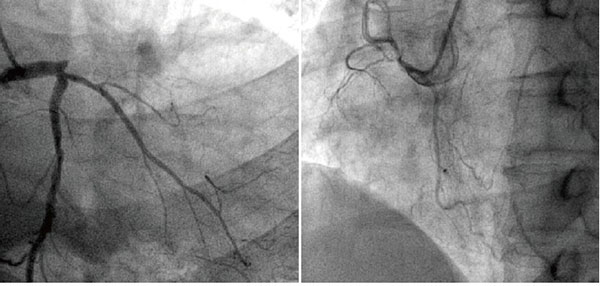

冠脈造影

冠狀動(dòng)脈是給心臟供血的血管,當(dāng)這個(gè)血管或者它的分支出現(xiàn)病變,我們就會(huì)患上冠心病(心肌缺血)。在輕度病變的時(shí)候, 患者沒有癥狀,或者出現(xiàn)心絞痛。嚴(yán)重病變的時(shí)候會(huì)有形成心肌梗死的風(fēng)險(xiǎn)。

前臨床常用的冠狀動(dòng)脈造影檢查包括冠狀動(dòng)脈CT血管造影(CTA)和介入冠狀動(dòng)脈造影兩種,都是評(píng)價(jià)動(dòng)脈是否存在病變以及指導(dǎo)治療的重要手段,兩者各有優(yōu)缺點(diǎn),也各有利弊,在不同情況下選擇不同的檢查方式,需要根據(jù)情況來(lái)決定,不能一成不變的認(rèn)為CTA好或者介入造影更好。